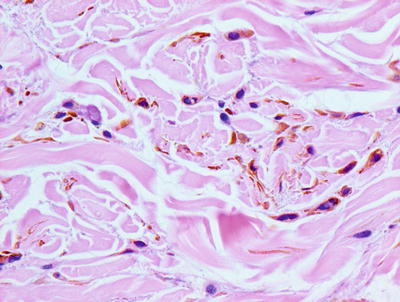

20.11.2 Histology

Histologic findings consist of a loose aggregation of densely pigmented, dendritic-shaped melanocytes within the superficial portion of the reticular dermis (Figs. 20.20 and 20.21). The melanocytes tend to course singly and do not form nests. There is no intraepidermal melanocytic proliferation. Cytologic atypia and mitotic activity are not present. The changes are indistinguishable from those of nevus of Ito, and the distinction is made on the basis of the affected anatomic body site. An attempt to classify nevus of Ota into subtypes based upon the depth of the lesion has not been widely incorporated into diagnostic practice [76].

Fig. 20.20

Sparse numbers of densely pigmented and spindled melanocytes are present in the superficial dermis in nevus of Ota. The epidermis may be uninvolved or may demonstrate increased basilar melanin

Fig. 20.21

Spindled melanocytes and melanophages course individually between reticular dermal collagen bundles in nevus of Ota